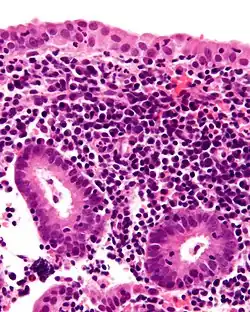

![]() Zapalenie błony śluzowej macicy, obraz mikroskopowy | |